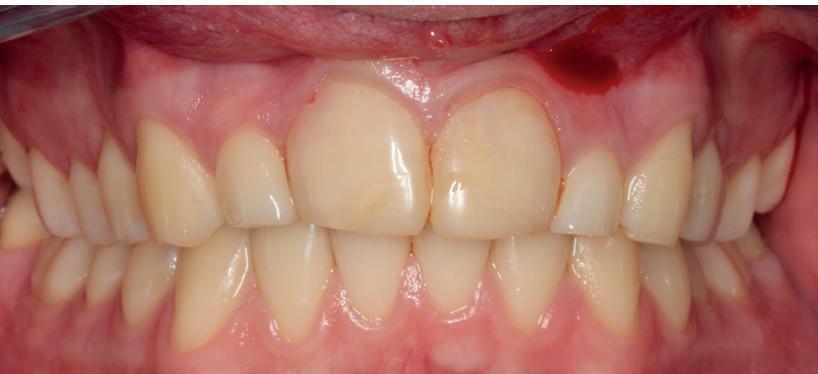

Mevrouw werd naar het Dental Design Center verwezen om een complex probleem aan het bovenfront te beoordelen en indien mogelijk te behandelen. Tien jaar geleden zijn er om esthetische redenen op de 12, 11, 21 en 22 kronen geplaatst. Helaas bleek achteraf een wortelkanaalbehandeling van de 22 noodzakelijk. Na een aantal jaar ontstond er weer een infectie apicaal aan de 22 en werd er een apex uitgevoerd. Helaas had deze behandeling niet het beoogde resultaat. Twee weken voordat ze bij mij op consult kwam, is het element geëxtraheerd en is er een partiële plaat geplaatst als tijdelijke oplossing (foto 1-3).

Na de IPP (esthetisch/functionele) analyse blijkt dat de gezichts- en faciale mediaan niet geheel overeenkomen en dat de gingiva lijnen van het bovenfront niet helemaal parallel lopen met de interpupillaire lijn. Na overleg met mevrouw kiest zij ervoor om dit niet orthodontisch te laten corrigeren. Mevrouw

heeft de nadrukkelijke wens om geen brugconstructie te krijgen. Om die reden is een etsbrug of een conventionele brug geen optie. Daarom bestaat het behandelvoorstel uit vier losse kronen waarvan de 22 implantaat gedragen zal zijn. Een gedetailleerd onderzoek van de regio 22 is noodzakelijk (foto 4-6).

De flap en graft worden met poly-propelene 6.0 hechtingen gefixeerd. De tijdelijke reconstructie wordt herplaatst (foto 17-20).

Na 4-6 weken kan het aangebrachte healing abutment worden vervangen door een tijdelijk abutment. Deze wordt aan de kunststof reconstructie verbonden om zo de gingiva ter plaatse van de 22 te vormen. Zo lijkt het of er geen implantaat maar nog steeds een wortel aanwezig is, wat het esthetisch eindresultaat ten goede zal komen (foto 21-23). Vanaf 4-6 maanden ziet het weefsel er gezond uit. Nu kan met de uiteindelijke restauratiefase worden gestart (foto 24 en 25).